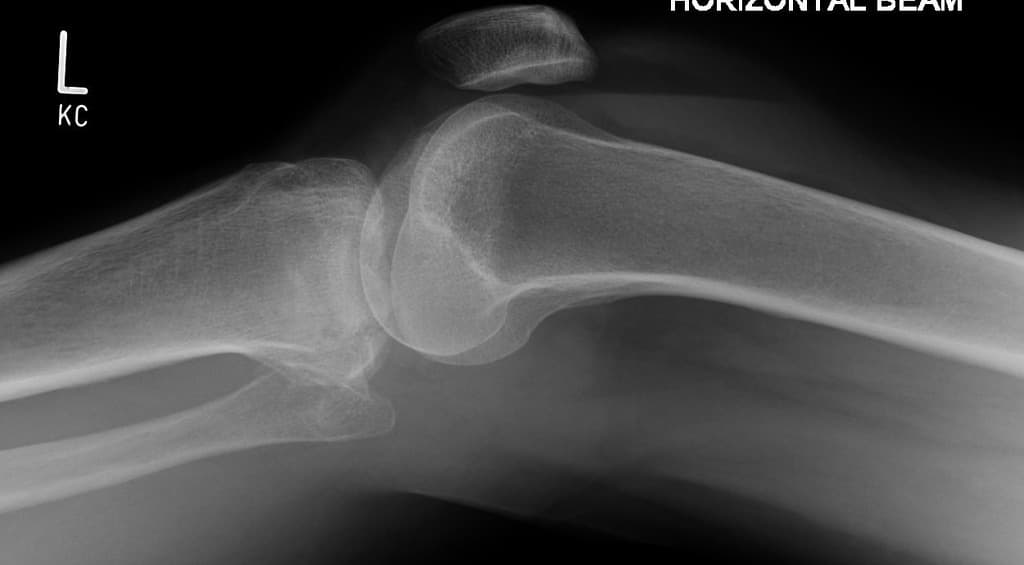

- Nhiều vùng tổn thương hình địa lý bất thường về tín hiệu tủy xương với dấu hiệu đường đôi (double line sign) và dấu hiệu viền (rim sign), là những đặc điểm điển hình của hoại tử vô khuẩn (avascular necrosis).

- Mũi tên hình mũi tên mở (open arrow) = dấu hiệu đường đôi (double line sign); Mũi tên đơn (simple arrow) = dấu hiệu viền (rim sign)

Bệnh nhân trẻ này là người nhận tủy xương và đang điều trị bằng corticosteroid liều cao, đã phát triển hoại tử vô khuẩn lan tỏa (extensive avascular necrosis) tại khớp gối.

Hoại tử vô khuẩn khớp gối (avascular necrosis of the knee)

Hoại tử vô khuẩn khớp gối là tình trạng bệnh lý do thiếu máu nuôi xương dưới sụn, dẫn đến chết tế bào xương và có thể gây sụp khớp nếu không được điều trị. Bệnh thường liên quan đến việc dùng corticosteroid, nghiện rượu, các bệnh về huyết sắc tố và ghép tủy xương trước đó. Trong trường hợp này, bệnh nhân dùng steroid liều cao sau ghép tủy xương làm tăng nguy cơ mắc bệnh. Chụp cộng hưởng từ (MRI) là phương tiện hình ảnh nhạy nhất, với các dấu hiệu điển hình như tổn thương tủy xương hình địa lý, dấu hiệu đường đôi và dấu hiệu viền. Chẩn đoán sớm rất quan trọng để can thiệp bảo tồn khớp như giải áp tủy xương hoặc cắt xương. Các chẩn đoán phân biệt bao gồm hoại tử xương tự phát khớp gối (SONK), thường gặp ở phụ nữ lớn tuổi và thường khu trú một bên, và hội chứng phù tủy xương, không có các thay đổi cấu trúc như trong hoại tử vô khuẩn.